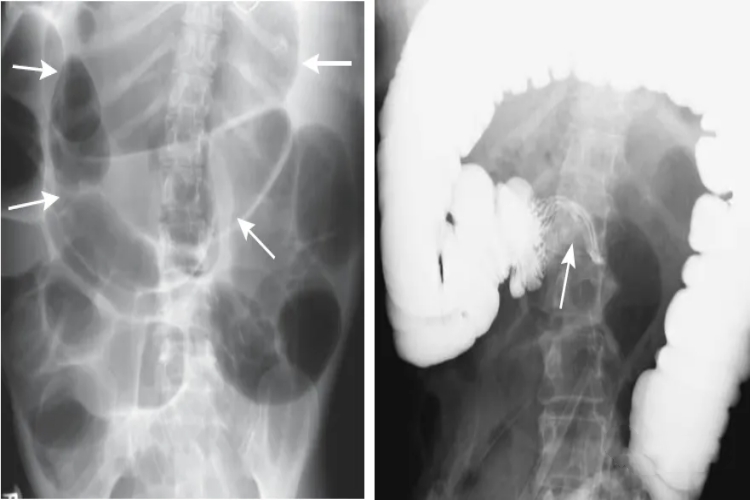

鸟嘴征多是因为肠扭转引起,导致扭转近段长肠管呈锥形逐渐变细,在靠近梗阻部位达到最细,呈现“鸟嘴”样改变。

鸟嘴征多是由于肠扭转引起梗阻部位两端肠管呈渐进性狭窄,至梗阻部位完全梗阻,行检查时钡剂无法通过,而呈现逐渐缩窄的鸟嘴征。